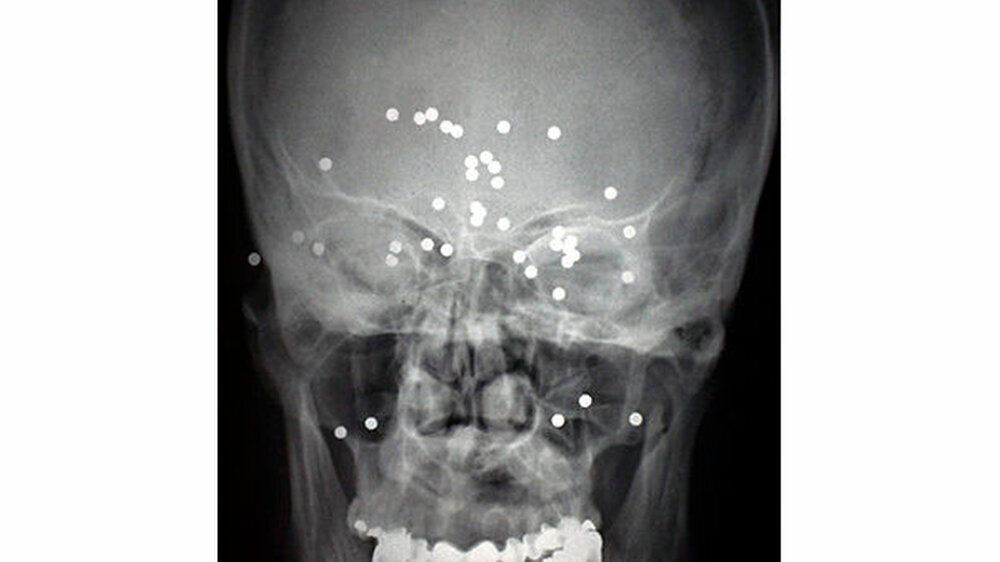

Fremdkörper im Gesicht

Vom Bohrer im Kopf bis zum Schlüssel in der Kieferhöhle: Die MKG-Chirurgen der Charité haben ausgewählte Patientenfälle mit Fremdkörpern im Gesicht zusammengestellt. In unserer Fotostrecke finden Sie die eindrucksvollen Aufnahmen.